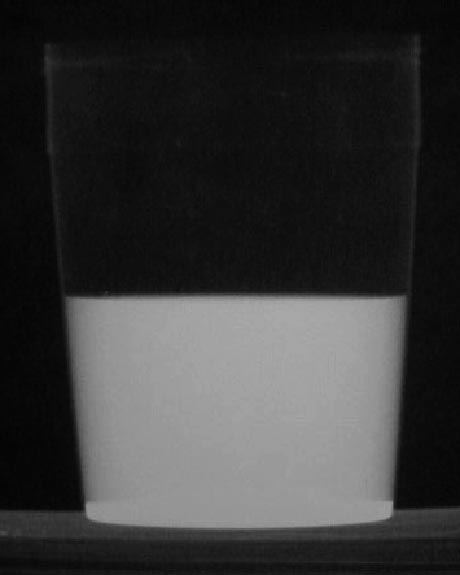

La demostración de una fístula colo-vesical puede ser difícil con radiología. El enema opaco, la cistografía y la TC pueden no llegar a demostrarla. Sin embargo, la presencia de contraste baritado tras un enema opaco en una muestra de orina, detectado mediante una radiografía de la muestra, es signo de fístula colo-vesical, aunque no se demuestre ésta con otros métodos de imagen.

La fotografía muestra un líquido de alta densidad en un tarro de orina, con un poso de bario en el fondo.